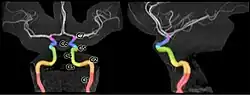

Angiograma por Resonancia Magnética.